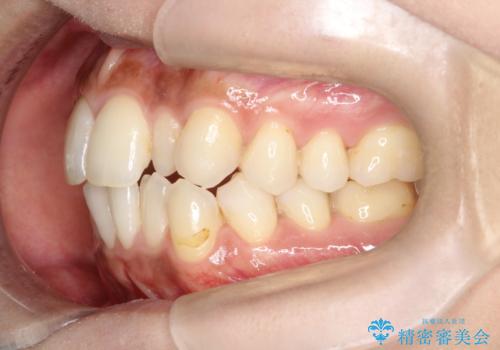

【インビザライン】矮小歯を有する方の矯正治療

- 前歯の凸凹を主訴に来院されました。

元々、歯が小さかったため矯正終了後にセラミックにて修復治療を行う治療計画をたてインビザラインにて治療を行いました。

今回はスペースを作るために歯列の拡大をメインでおこなっています。